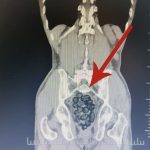

Durumundan şüphelenilen yabancı uyruklu bir yolcu üzerinde arama yapıldı. Yapılan incelemeler sonucunda yabancı uyruklu şahsın midesinde 64 Parça halinde toplam 472 gram uyuşturucu maddesi metamfetamin olduğu belirlendi.

Gözaltına alınan şahsın midesindeki uyuşturucu madde çıkartıldı. Emniyetteki işlemlerinin ardından adliye sevk edilen şahıs, çıkarıldığı mahkemece tutuklanarak cezaevine gönderildi.